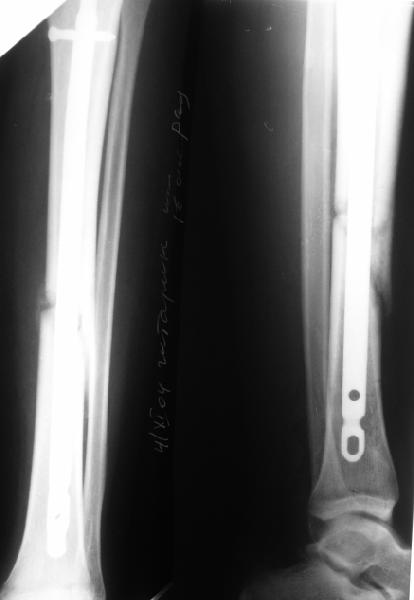

Уважаемые коллеги,пожалуйста, подумайте над следующим ребусом. В нашу клинику поступилпациент из области, 17лет, получивший травму в ДТП 25.08.04, открытый перелом бедра, при поступлении наложено скелетное вытяжение.

30.09.04 на операции выявлен вывих бедра и перелом голени на этой же стороне. Остесинтез бедра все же выполнен, и по заживлении раны пациент переведен к нам. Кроме того у пациента нейропатия седалищного нерва на этой же стороне. В нашей клинике планируется наложение аппарата таз-бедро, для постепенного низведения бедра с последующим открытым вправлением, замена фиксатора на запираемый гвоздь и блокируемый остесинтез голени. Вариант с первичным эндопротезированием мы не рассматривали из-за юного возраста пациента. Вопрос с чего начать? Кроме того, сгибание в коленном суставе в настоящее время (95 градусов) затрудняет остеосинтез голени.Стоит-ли менять гвоздь? Или же спилить торчащий конец во время открытого вправления? Может, попробовать все сделать одномоментно? Заранее спасибо.

Просьба простить за длительное молчание, не было фотоаппарата, чтобы перенести рентгенограммы. Больного прооперировали в прошлый четверг, как и предполагали, голень проблем не доставила(настолько, что даже не ввели дистальные винты по ряду причин: срок после травмы, целая малоберцовая, последующая длительная ходьба без нагрузки, да и гвоздь сел плотно). Изначально планировали после удаления фиксатора антеградно завести стержень и утопить конец, но вопрос был исчерпан, когда выяснилось, что все имеющиеся стержни слишком длинные, пришлось ретроградно забить большеберцовый гвоздь, после рассверливания; серьезные проблемы возникли с устранением ротации. В вертельной области сломали стержень-джойстик(привет установщику эндопротеза), дальнейшие манипуляции проводили пучком спиц и стержнем с кондуктором. Закончили все аппаратом таз-бедро. Решили что возможные огрехи с ротацией устраним после открытого вправления. Снимки прилагаю. Спасибо за участие в обсуждении. Обязуюсь информировать о дальнейших этапах лечения.